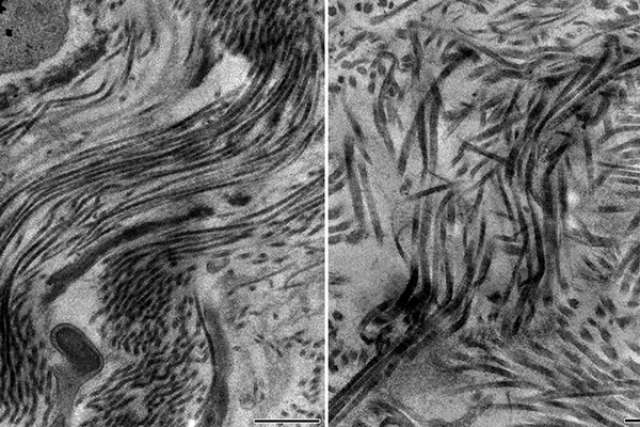

Electron microscopy images show (left) a healthy scar containing collagen type 5, with scar fibers smoothly arranged in parallel, and (right) an unhealthy scar containing no collagen type 5, with a disorganized architecture and disarray of scar fibers.

New UCLA research conducted in mice could explain why some people suffer more extensive scarring than others after a heart attack. The study, published in the journal Cell, reveals that a protein known as type 5 collagen plays a critical role in regulating the size of scar tissue in the heart.

Digging deeper, Deb and his collaborators from the Geffen School of Medicine, the California NanoSystems Institute at UCLA and the UCLA Division of Life Sciences found that type 5 collagen was regulating the stiffness of scar tissue. Without it, the scar tissue was less stiff and therefore prone to expansion from the force of the blood within the heart.